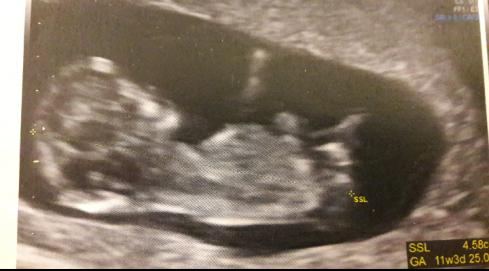

I will share two beautiful pictures of our first miracle :fami03:

As we are soo excited, we would love to get to know if we expect a little prince or princess.